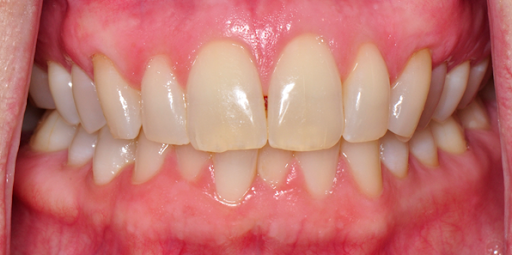

Dental X-ray showing a pneumatized right maxillary sinus with red markings highlighting certain areas.

Before